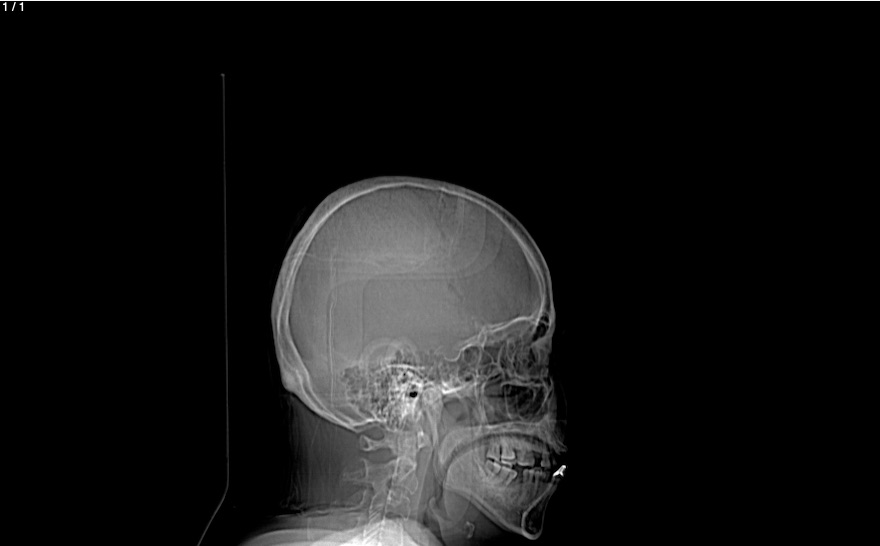

Bidelina Munoz Morales 54A - Unnamed